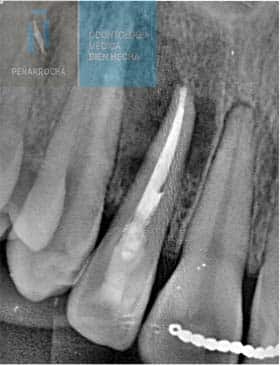

X-ray signs of a failed root canal treatment

One of the most reliable diagnostic tools for detecting root canal failure is dental radiography. With X-rays, the specialist can carefully examine the inside of the tooth and root canals to determine whether the treatment has been successful or if signs of failure are present.

Some of the most common radiographic signs of a failed root canal treatment include:

- Unfilled canals: an X-ray may reveal empty spaces along or at the end of the root canal that were not properly sealed. These gaps provide an entry point for bacteria, increasing the risk of infection and reinfection.

- Overfilling: when the filling material extends beyond the root apex, it can irritate the surrounding periapical tissues. On the radiograph, this appears as a white extension beyond the tip of the root.

- Dark areas around the root: dark or radiolucent zones in the bone surrounding the root are often a sign of infection or periapical lesions that compromise the bone structure.

- Periapical lesions: visible as darker or radiolucent areas around the tooth apex, periapical lesions indicate the presence of persistent inflammation or an active infection.

- Untreated canals: sometimes additional canals are missed during treatment. On an X-ray, they appear as radiolucent areas since they were not cleaned, shaped, or filled. Their presence can cause ongoing infection and treatment failure.

- Root fractures: although difficult to detect, root fractures may appear as fine, dark lines along the root. They can also cause irregular changes in the surrounding bone pattern, suggesting structural compromise.

In some cases, X-rays may show a radiolucent lesion around the apex of a tooth, even when the root canal appears to have been performed correctly. This suggests that, despite proper technique, the treatment has ultimately failed. A follow-up radiograph after apical surgery can often confirm the healing of the affected area.

In any situation, it is essential that an endodontist or oral surgeon evaluates the radiograph to accurately determine the condition of the tooth and whether additional treatment is required.